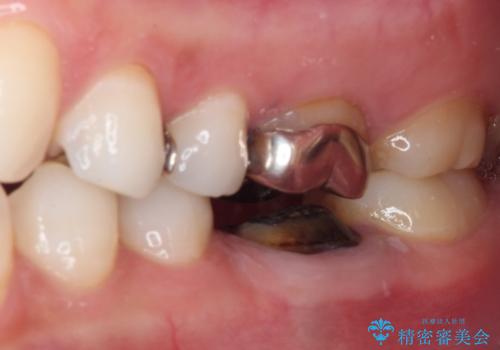

- 奥歯の銀歯が外れたことをきっかけに、全ての銀歯をセラミックに替えたいとのことで来院された患者様です。

第一大臼歯4本と、メタルインレーが装着されている2歯をセラミッククラウンならびにセラミックインレーにて補綴治療・修復治療を行うこととしました。